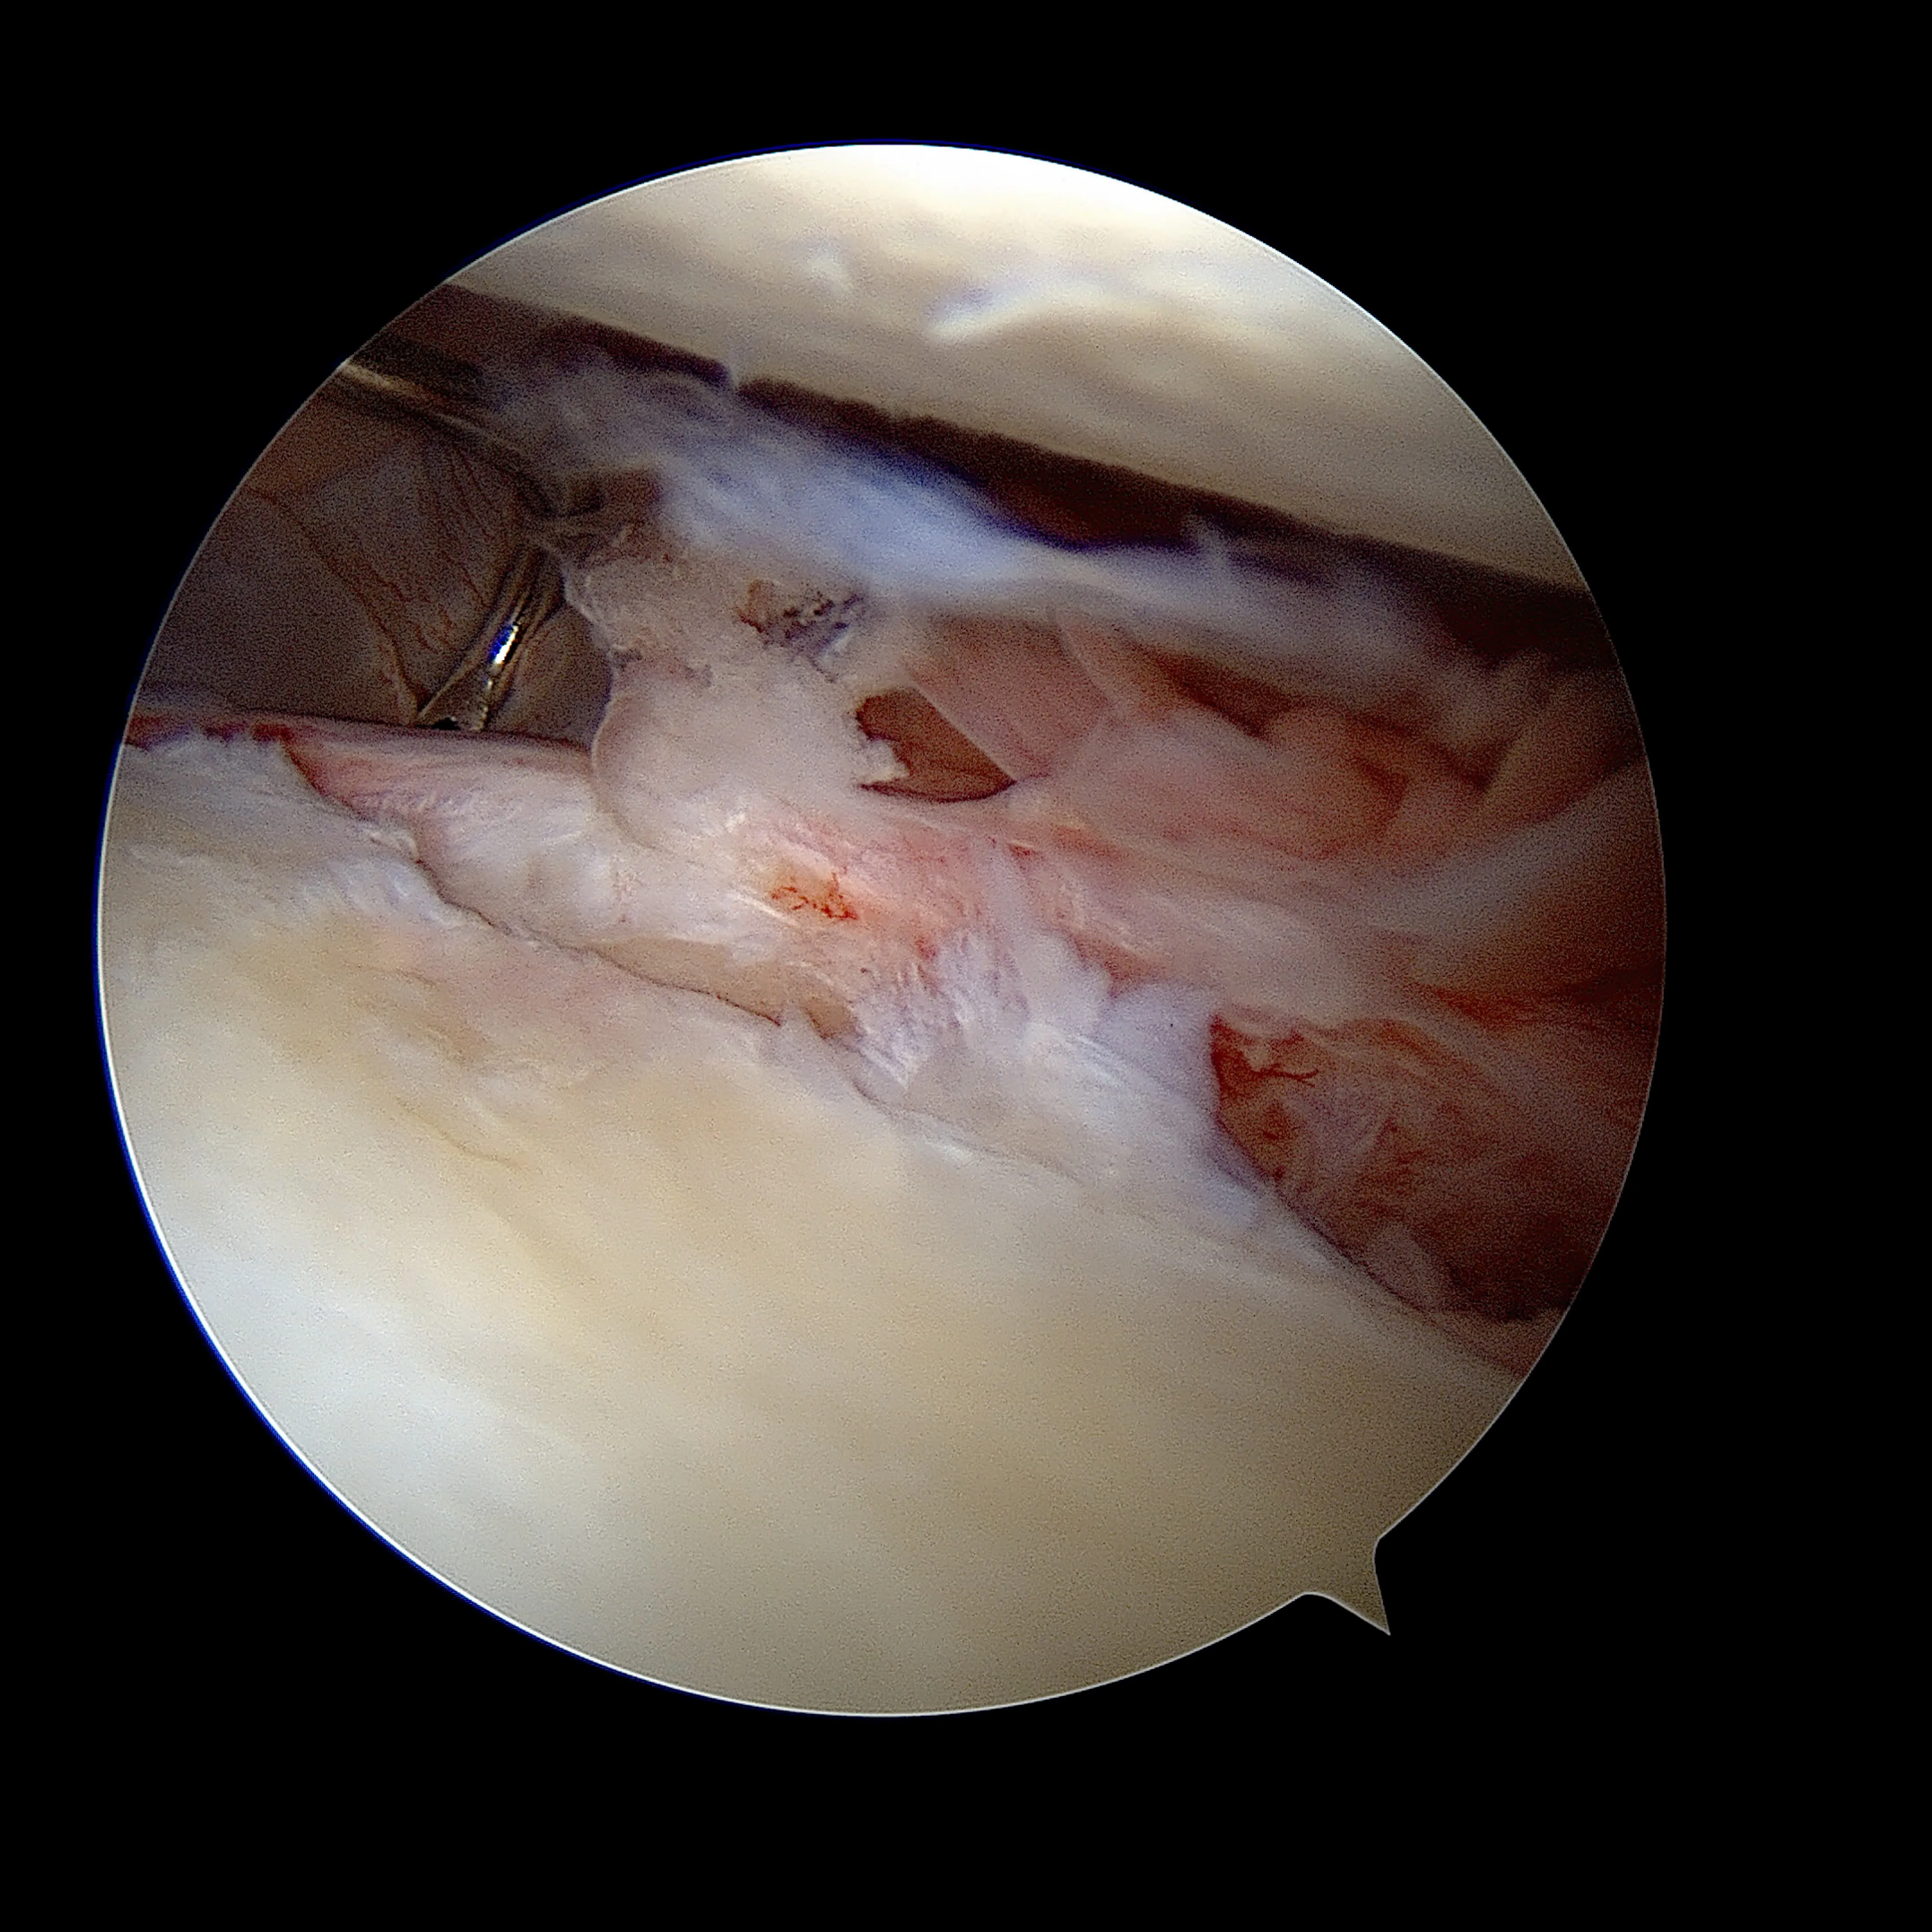

La lésion de HillSachs sous arthroscopie

Les lésions osseuses:

Lors d'un épisode de luxation, la tête humérale venant heurter violemment la partie antéro-inférieure de la Glène, elle peut provoquer une fracture du rebord osseux de celle-ci. Lorsque la tête humérale vient s'incarcérer en regard de la glène, Elle peut également s'écraser et se déformer de façon irréversible à la manière d'une balle de ping-pong que l'on écraserait avec le doigt.

Lorsque les déformation osseuse sont importantes les techniques arthroscopiques ne suffisent pas à stabiliser l'épaule. La technique la plus appropriée est alors la réalisation d'une butée coracoïdienne. L'association d'une technique arthroscopique de réparation du bourrelet , d'une rétention capsulo-ligamentaire et un comblement de l'encoche de Hill-sachs peut être une alternative dans certains cas.